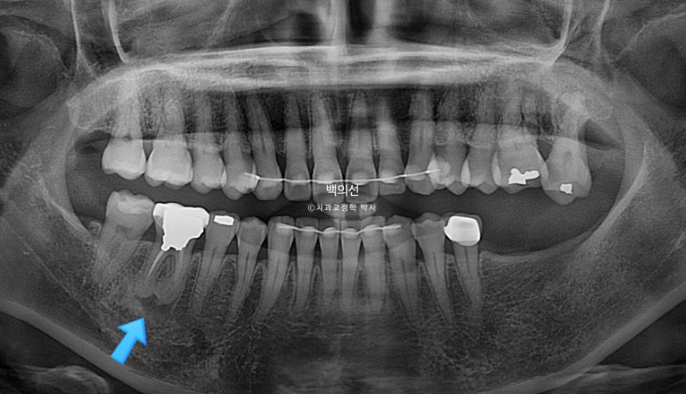

임플란트가 필요한 부분을 장기간 방치하면 대합치가 조금씩 솟아 내려오게 됩니다.

파란화살표 임플란트를 해넣기 위해서는 교정으로 내려온 대합치를 합입 시켜 올려야 합니다.

특히 내려온 큰어금니들 중 맨 뒤 제2대구치는 살릴 수 없어 타병원에서 발치진단이 나온 상태입니다.

잇몸이 뿌리끝까지 내려가 상태가 좋지 않습니다.

다른 문제가 하나 더 있습니다. 파란 화살표 치아는 신경치료 된 치아인데 뿌리끝에 염증이 있습니다.

파란화살표 문제의 치근단 염증은 초진에 비해 커지지 않고 잘 유지되었습니다. 치료계획상 이동이 전혀 일어나지 않도록 했기 때문입니다.

치근 평행도는 처음보다 좋아졌으며 치근흡수는 없습니다.